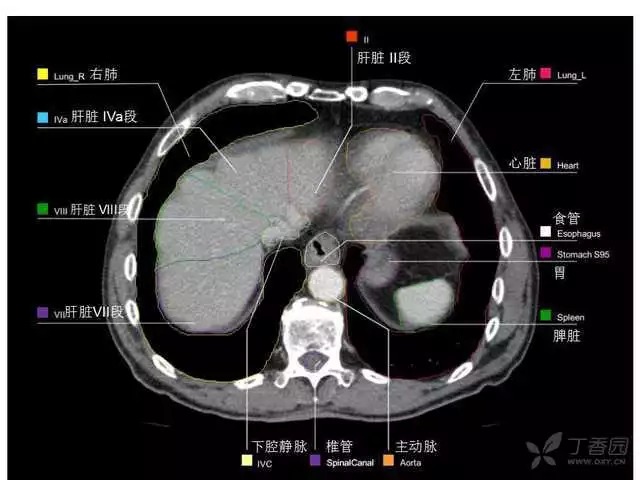

腹部肝脏高清CT断层的图谱

全腹部高清CT图谱,淋巴结彩色图谱,血管解剖图谱大汇总!

肝段,肝内管道的分布规律